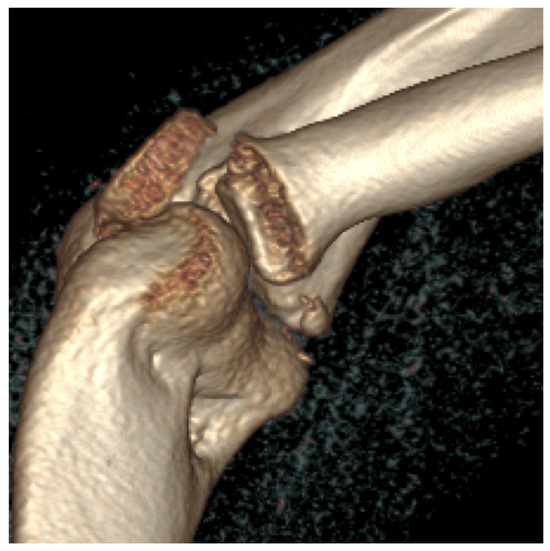

Third patient: A 17-year-old patient was admitted following a snowboarding injury that affected her elbow. Although the patient reported pain and swelling of the proximal forearm was visible upon inspection, the Moberg test was negative. The fracture of the radial head was confirmed by the initial X-ray, after which a CT was performed, which established a Mason type II fracture and dislocation of the radial head (Figure 7).

Figure 7.

The CT images confirm the Mason type II fracture and dislocation of the radial head.

Fourth Patient: An 11-year-old girl suffered a fall injuring her left elbow. During physical examination on the following day, swelling and bruising could be seen. Initial imaging with plain radiography revealed the fracture of the lateral epicondyle of the humerus with dislocation. CT imaging was requested for surgical planning and revealed the involvement of the capitulum and the trochlea. The surgery took place in exsanguinated conditions; it totalled 100 min. After disinfection and draping, we performed a radioventral approach just above the elbow. The capsule could be accessed ventrally, after passing through the brachioradialis muscle. By making a longitudinal incision on the capsule, we allowed for the hematoma to clear, which we washed several times with physiological saline for better visualisation. After that, the upward dislocation of the capitulum humeri could be seen clearly. At this point, it is noted that the opening was too small for proper visualization and handling of the fragment; therefore, the incision was lengthened distally and to the ulnar side, leaving us with an S-shaped traditional approach. The biceps tendon and the brachial artery were held out of the way with the aid of equipment to avoid damage and disturbance from repositioning. At this point, the fracture affecting the trochlea became visible. Following repositioning, we drilled three holes with the aid of K-wires for one 1.5 × 20 mm and two 1.5 × 25 mm absorbable nails. Two nails were placed in the capitulum humeri and one into the trochlea to reach final stabilisation. Before closure, we tested for the passive extension and flexion of the elbow joint, which was performed to full ROM without any notable interference. The capsule was then reconstructed and the exsanguination was stopped. The brachioradialis was then inspected and no signs of major bleeding were identified. Subcutaneous layers were reconstructed with absorbable 3/0 thread while the skin was reconstructed with 4/0 non-absorbable thread and an intracutaneous approach. After the application of bandaging with Bactigras, a 90-degree dorsal cast with a U-splint was placed on the left arm; this was utilised for four weeks. The post-op period was uneventful; neurovascular complications could not be identified; and one day after surgery, radiological findings showed the proper position of the fragment. Thus, the patient was returned to their home. Swelling and non-reactive scars were noted during the 1-week control examination; these slowly disappeared over the course of the next few weeks. Plain film radiographic controls were performed at weeks 3 and 6, which described the post-op state of a healing fracture with some decrease in ROM; however, after 4 months, the scar was healed but some locking was observed along with restricted ROM, with active movement possible between 70 and 110 degrees with proper capillary reflex. A CT examination was ordered, which revealed the normal healing of the capitulum humeri with a lytic lesion on the border of the capitulum and the trochlea. To improve functionality, subaquatic physiotherapy was started. In the 1-year control examination, the patient described better functionality with active motion of 40–110 degrees with continued physiotherapy. Control CT was performed after 2.5 years; it revealed the appropriate position of the elbow joint without any pathological findings or lesions.